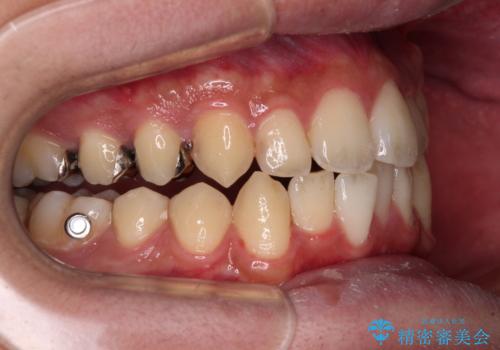

- 上下のクロスバイトと前歯のデコボコを気にして来院された患者様です。

インビザラインを用い、IPR(歯と歯の間を削る)と歯列全体を拡大させることで、歯並びを整えていくこととしました。

インビザライン特有の、治療後半に奥歯が咬み合わないという事象が長引きました。

咬み合わないときの対処方法は色々とありますが、ゴムかけなどを活用して噛めるようにしました。